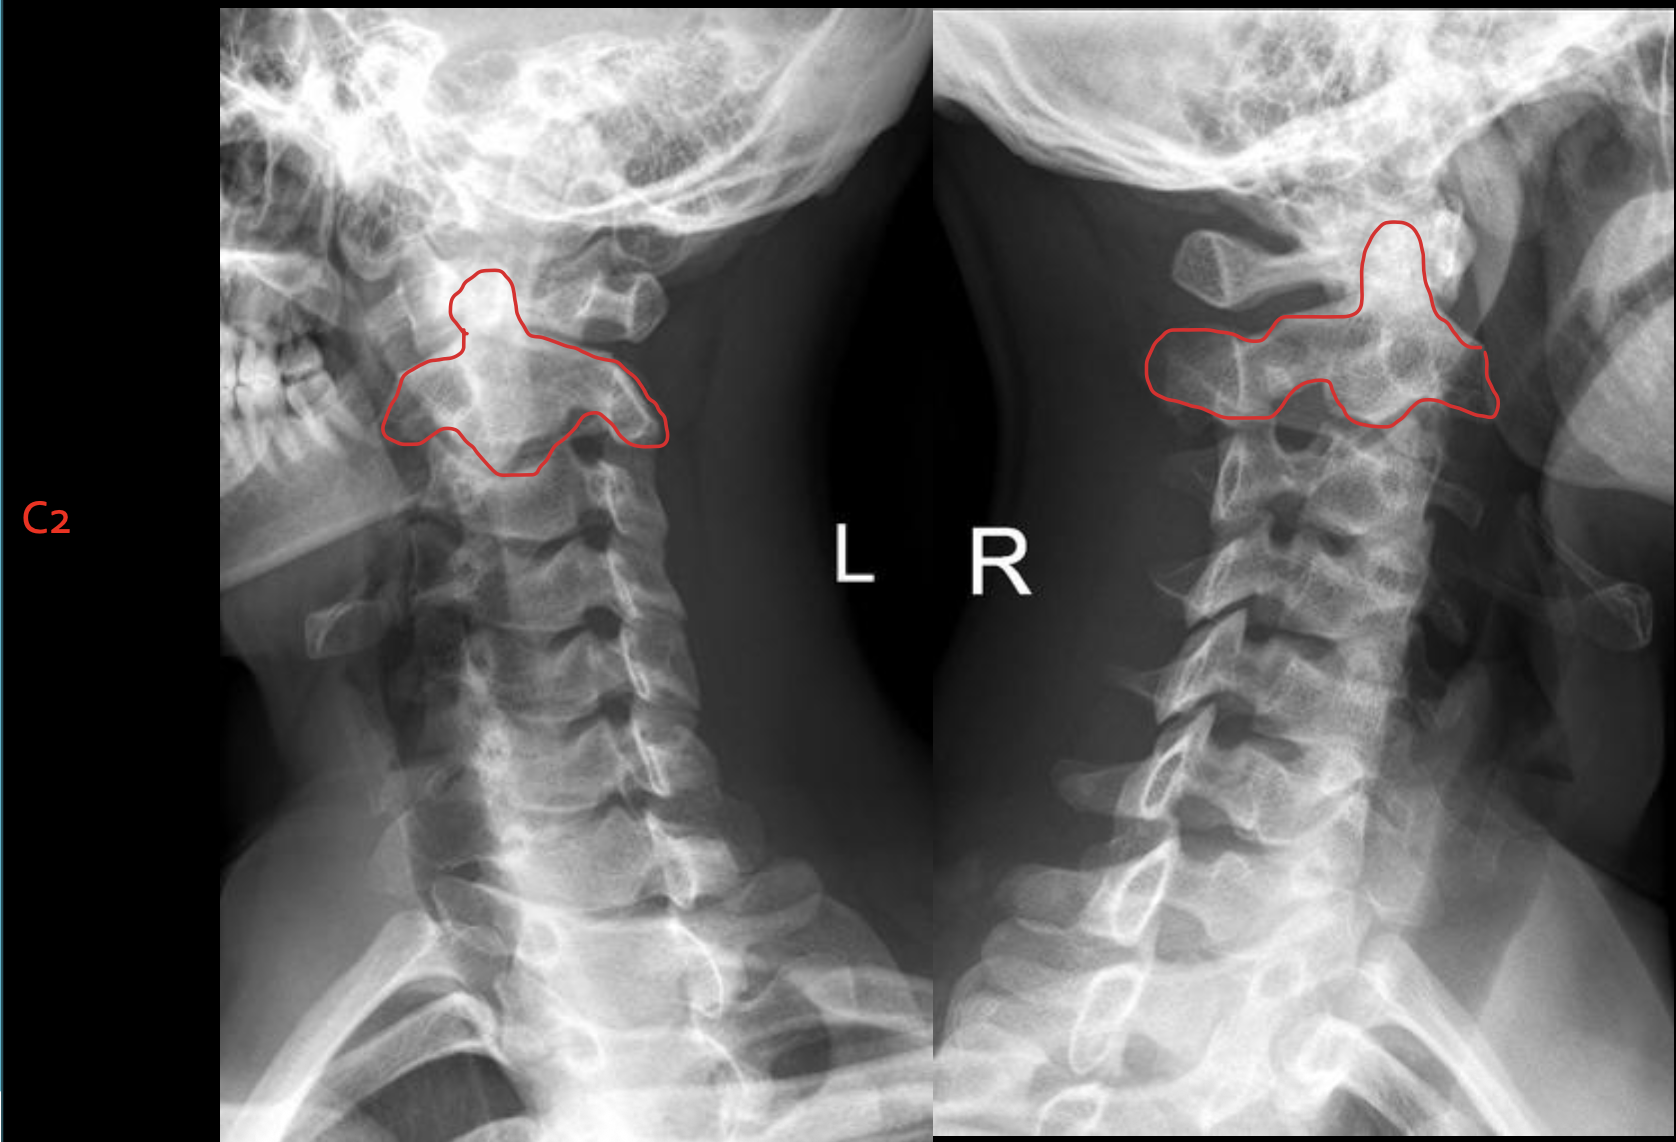

C2

齿状突

Odontoid process C1